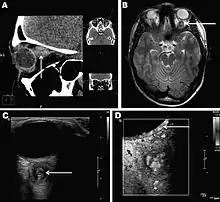

- ↑ Sven Poppert, Maike Hodapp, Andreas Krueger, Guido Hegasy, Wolf-Dirk Niesen, Winfried V. Kern, and Egbert Tannich (November 2009). "Dirofilaria repens Infection and Concomitant Meningoencephalitis". Emerg. Infect. Dis. 15 (11): 1844–1846. doi:10.3201/eid1511.090936. PMC 2857255. PMID 19891881.